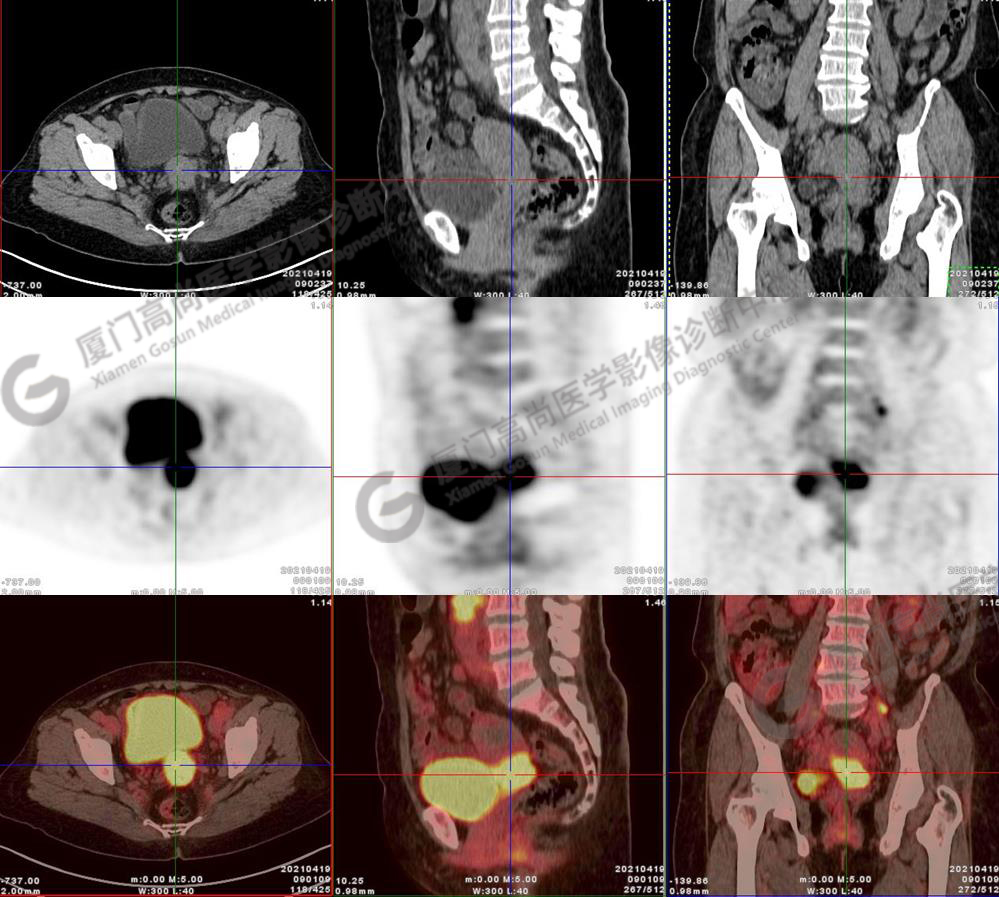

圖10-11:子宮頸軟組織腫塊,代謝異常增高,考慮為宮頸癌。

圖10

圖11

圖12-13:延遲2小時后,宮頸腫塊糖代謝進一步增高。

圖12

圖13